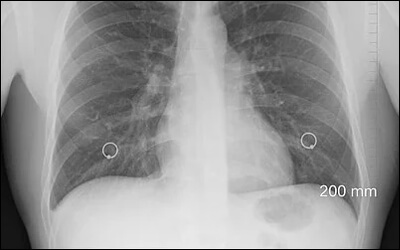

심낭염이 의심되는 경우에는 흉부 x-ray 촬영, 심전도 검사와 혈액 검사를 진행합니다. 흉부 x-ray와 심전도 검사는 일반 병원이나 의원에서도 비교적 쉽게 받을 수 있습니다. 심낭염인 경우 흉부를 촬영했을 때 심장이 커진 모양을 확인할 수 있으며, 심전도에서 심낭염의 특징적인 소견을 체크할 수 있습니다. 심장 초음파는 대형 병원에서 검사를 받아야 하므로 응급인 경우 심낭의 삼출을 찾는 데 사용됩니다.